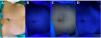

Hipomelanosis macular progresiva y confluente en la paciente2. A)Presentación clínica de las lesiones bajo luz ambiental. B)Coloración azulada de las lesiones con lámpara de Wood convencional. C)Coloración blanco-azulada de las lesiones con linterna LED de 365nm: óptima delimitación de las lesiones. D)Coloración azulada de las lesiones con luz azul emitida por smartphone: subóptima delimitación de las lesiones por exceso de brillo.

Comparando las tres técnicas, con la linterna LED 365nm se observó la mejor delimitación de las lesiones, sin adquirir la tonalidad azulada percibida con el resto de dispositivos. Utilizando la luz azul del teléfono móvil se apreció cierta mejoría en la delimitación de las lesiones, pero se objetivó un exceso de brillo en ambos casos, lo que dificultó su delimitación (tabla 1).